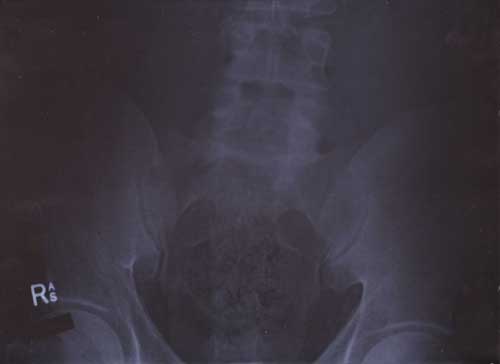

21st January 2000

22nd January 2000